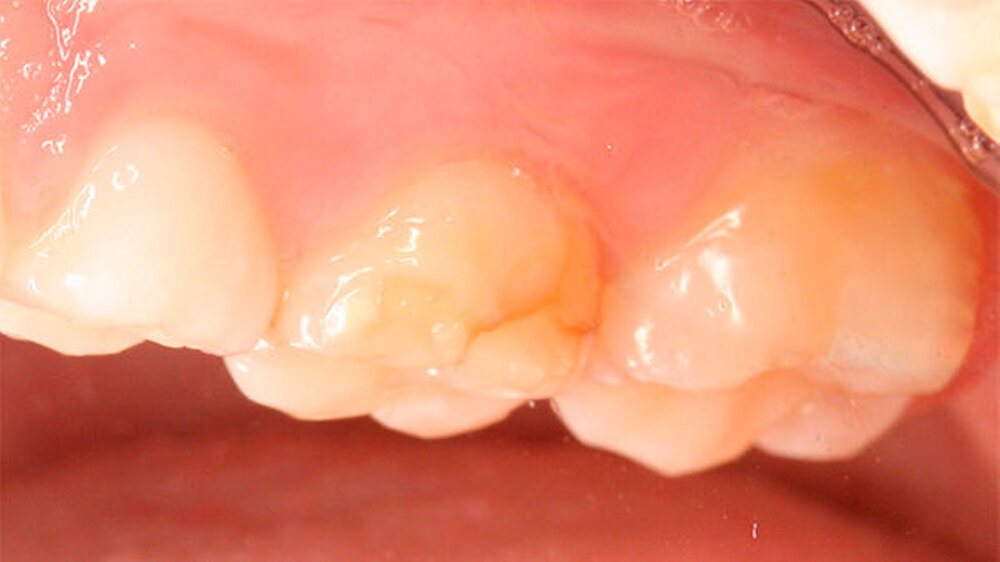

Zusätzlich zu den Frontzähnen waren die Molaren in sehr unterschiedlicher Ausprägung betroffen. Dies reichte von lediglich kleineren Opazitäten bis zu darüber hinausgehenden Schmelzverlusten: Im ersten Quadranten war Zahn 16 klinisch vollkommen unauffällig, hier zeigte aber der zweite Milchmolar insbesondere bukkal Opazitäten und Einbrüche des Schmelzes (Abbildungen 3 und 4) auf.

Zu ergänzen ist, dass die mesio-bukkale Opazität an Zahn 65 zwischen dem Zeitpunkt der Aufnahme der Patientin und der Präparation wenige Wochen später einen Einbruch der Schmelzoberfläche aufwies (Abbildungen 4 bis 6).